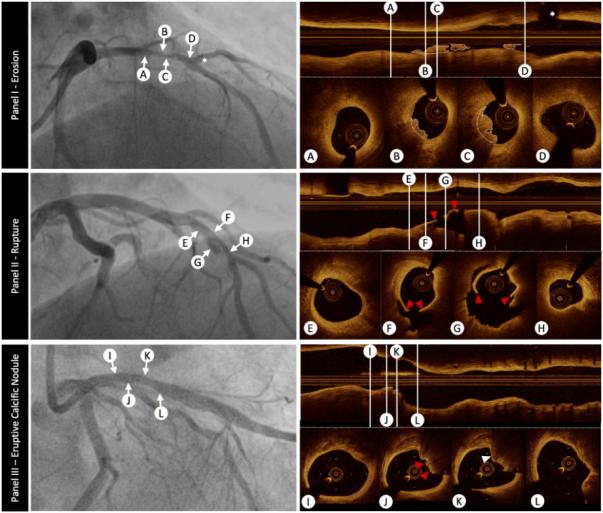

另外,CLIMA研究表明,OCT凭借极高的分辨率可以识别斑块精细特征(图2),包括薄帽纤维粥样斑块、富脂质斑块、巨噬细胞等与不良预后相关的高危斑块等特征,目前将具有上述特征的斑块统称为易损高危斑块。相比OCT,目前的常规影像学手段识别的易损斑块特征的临床应用价值受限于其较低的不良事件预测价值。

图2 左:冠脉造影,右:OCT;自上而下分别是斑块侵蚀、斑块破裂、钙化结节